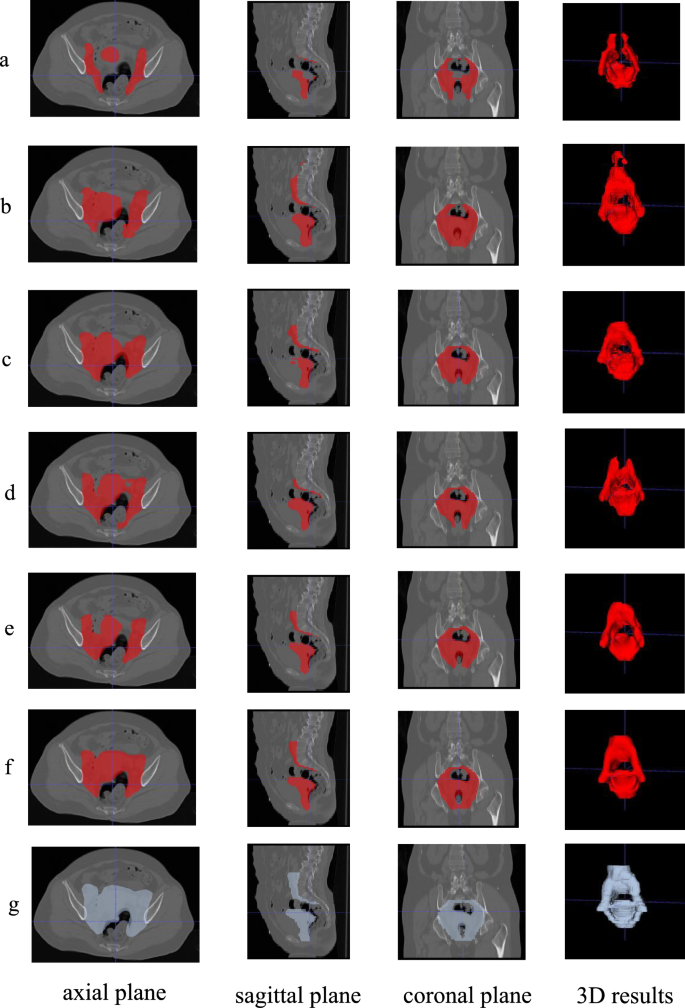

We randomly selected samples and visualized the prediction results in Fig. 5. It can be seen that the baseline network can identify the general area of cervical cancer CTV, but the segmentation performance at the edge is poor, which is consistent with our hypothesis. As shown in Fig. 5(a), 3D-UNet performs poorly at the upper boundary, where the distance outlined along the abdominal aorta is short and the outer edge of the uterine body morphology at the front boundary is not obvious. In contrast, our method shows significant improvement at the segmentation edge. The possible reason is that SCN learns the relative position relationship between the OARs and CTV, providing meaningful guidance for the segmentation of CTV. WAN helps to further improve the segmentation accuracy of the network by learning the anatomical prior knowledge between the psoas muscle and CTV.

Comparison of different methods for segmenting CTV. (a) 3D-UNet, (b) nnFormer, (c) UNETR, (d) 3D-UXNet, (e) nnU-Net, (f) Our method, (g) Ground-truth.